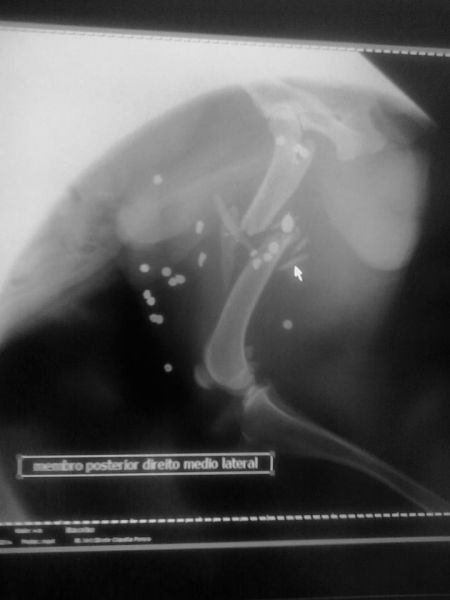

Um cão foi ferido por diversos chumbos provenientes de tiro de espingarda. O fato ocorreu na noite do último sábado (04) no Centro de Piratuba. O proprietário do animal, Helmuth Heinrich Schmitt, morador da rua Santa Catarina, denunciou o crime. Ele disse que possui dois cachorros dóceis que atendem pelo nome de “Bubi” e “Trixi”. Schmitt, que é natural da Alemanha e reside em Pirtuba desde julho de 2012, ressalta que “Bubi” fugiu de casa e retornou no dia seguinte alvejado um tiro de espingarda. O animal foi levado a uma clínica veterinária em Piratuba e posteriormente a uma clínica de Concórdia, onde exames detectaram cerca de 20 projéteis na parte superior da pata direita traseira, inclusive com fratura de osso. Diante da gravidade dos ferimentos o cachorro foi encaminhado para uma clínica especializada em Xanxerê, onde passou por cirurgia e está em fase de recuperação. O cão tem cinco anos. Revoltado com o fato e pelo uso de arma de fogo contra animais no Centro da cidade, Schmitt registrou boletim de ocorrência da delegacia de Polícia de Piratuba. Schmitt revela que até ouviu um tiro, mas jamais pensou que seria contra seu cachorro. “Eu penso, à noite atirar em cachorro com espingarda, arma é ilegal, pessoa com arma ilegal é criminosa, pessoa com arma ilegal é perigosa, pode atirar em outras pessoas”. Schmitt é policial aposentado e foi professor de tiro na Alemanha e escolheu a cidade de Piratuba para morar com a esposa, e afirma ter ficado decepcionado com o fato.